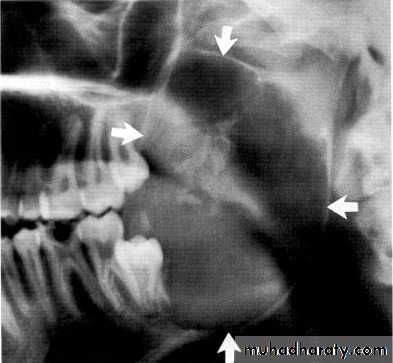

Ameloblasoma*Non-metastasizing tumor originating from remnants of the odontogenic epithelium of the enamel organ or dental lamina. *Associated with the crown of impacted teeth.

*80% located in the bicuspid & molar regions.

*Shape: is either unicystic or soap bubble-like lesion, Expansile, *Tooth migration is common,teeth in the area are vital.

*Adjacent teeth displaced, loosened , often resorbed

Extensive expansion in all dimensions

Maxillary lesions can extend into the paranasal sinuses, orbit or base of the skull.

Male > female.

Age; > 30 years